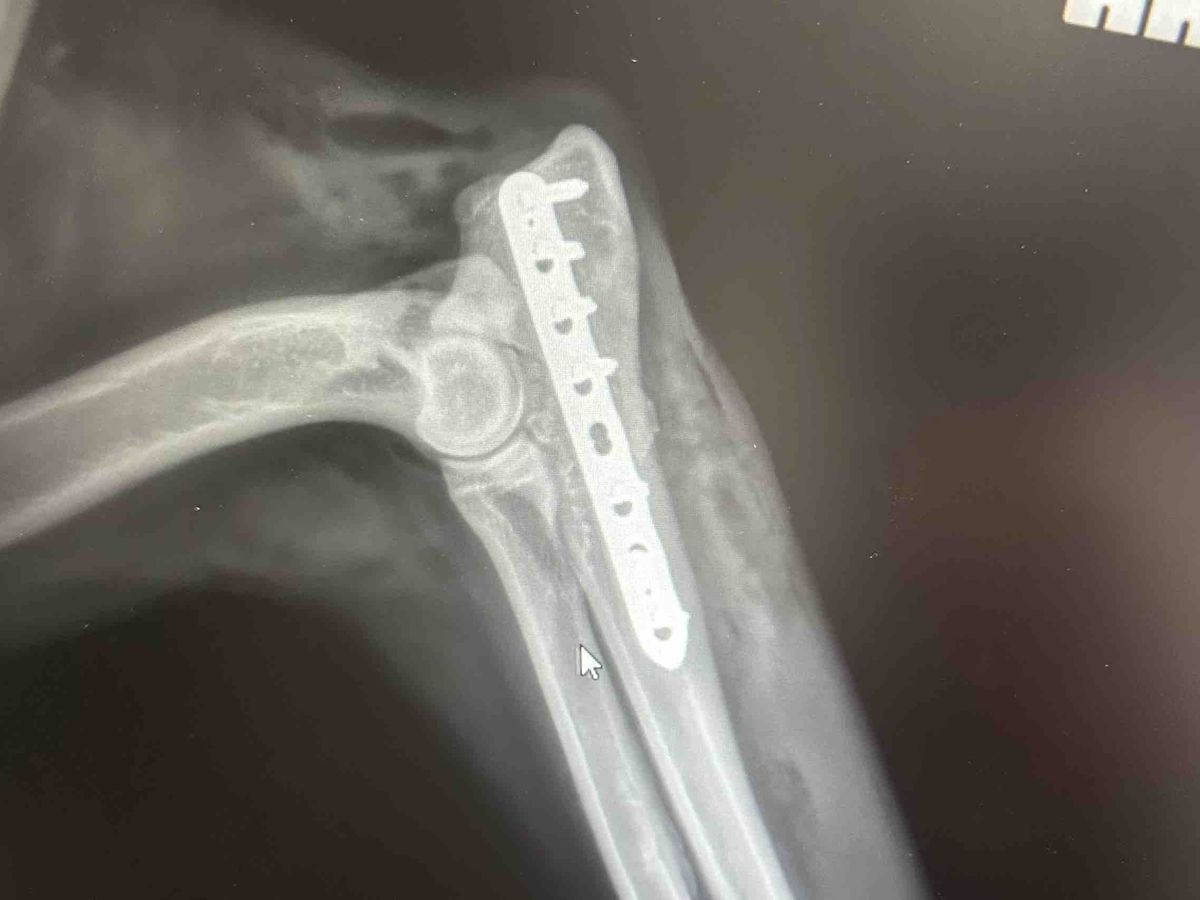

Hi my name is Carter I am a 15 year old boy. I’m trying to raise money for my dog. Her name is Bella, she is a 1 year old puppy and she broke her elbow. She had to get surgery and got a plate in her leg. She loves to play golf and loves anything to do with golf balls. Every time we go out to play we always play golf. I hit the golf balls to the field by my house and she runs after and brings them back for me. One day we were out playing, I swung my club and she stepped in front of the ball too soon and the ball hit her on the elbow. Me and my mom took her into the vet and they told me that her elbow was broken. The vet surgeon gave me three options. Put her down, amputate her leg, or she gets surgery to fix the break in her leg. I chose to get the surgery so that she could live the most normal life possible. She’s very active and wants to play all the time.